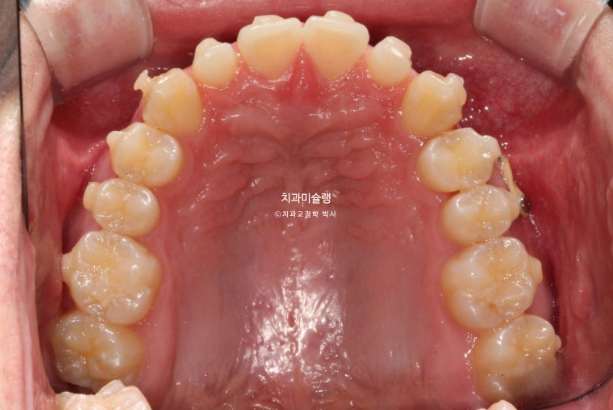

파란 화살표가 가위교합이고 위 큰어금니는 바깥으로 나가있고 대합치는 안쪽으로 쓰러지며 가위처럼 서로 엇갈려 교합되는 상태를 말합니다.

파란 화살표 치아가 바깥으로 뻗치면서 가위교합의 원인이 됩니다.

가위교합은 해결이 되었지만 아직 어금니 교합이 긴밀하지 않습니다.

배열은 완벽합니다.

중심선 등을 좀 더 바로잡고자 재제작에 들어갑니다.